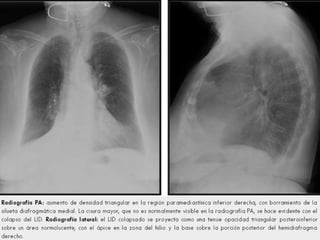

Signos directos

 Desplazamiento cisural, cuando la atelectasia

es lobar, las cisuras se retraen hacia el lugar

afectado.

 Pérdida de la aireación, que se observa como

una imagen radiopaca en el lugar afectado.

 Signos broncovasculares, debido a la

retracción pulmonar hay apelotonamiento de

vasos al nivel de la lesión.

Signos indirectos

 Diafragma, elevado en el lado de la lesión.

 Tráquea, Hilio y Mediastino desviados hacia

el lado de la lesión.

 Espacio intercostal, disminuido debido a

que la trayectoria de las costillas, sobre

todo en el extremo anterior, se hace más

oblicua.

 Enfisema compensador, debido a que el

área adyacente o el pulmón contrario sufre

hiperinsuflación